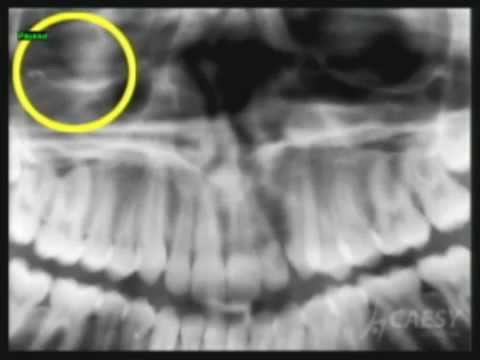

Dental X-Rays Linked To Brain Tumors In New Yale Study

Dental X-Rays Linked to Brain Tumors in New Yale Study ABC News. Subscribe Subscribed Unsubscribe 1,628,752 1M. Having a Dental X-ray - Duration: 4:09. The Royal Children's Hospital Melbourne Rockford IL Dentist Shares Ask Dr. Oz Teeth Segment on Grinding in Children ... View Video

RISK MANAGEMENT INTEL REPORT – Dental X-rays Page 1 of 2 a correlation between dental X -rays and meningioma, a non-malignant brain tumor. • Keep records of X-ray exposure • Maintain the equipment • Train the staff . ... Read Here

AAOMR Response to Recent Study on Dental X-ray Risks a benign tumor arising in the brain (Claus EB, Calvocoressi L, Bondy ML, Schildkraut JM, Wiemels JL, Wrensch M. Dental X-Rays and Risk of Meningioma). This population- diagnostic tool in the armamentarium of the dentist, ... Content Retrieval

1910 North Penn Road, Hatfield, PA 19440 USA Tel 888-883-3947, Fax 888-833 up by national media. The study associated an increased risk of developing meningioma (a commonly diagnosed type of brain tumor) with dental X-rays. The American • Newer generation X-ray units reduce ... View This Document

Spring 2012 Newsletter From Premier Dental Associates DENTAL ...

Spring 2012 Newsletter from Premier Dental Associates (877) RITA-DDS DENTAL XRAYS DEBATE Since Reuters published “Dental x-rays linked to common brain tumor” study Because many diseases of the teeth and surrounding tissues cannot be seen when your dentist examines your mouth, an X ... View Document